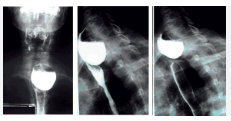

Exame contrastado de esôfago em andamento

Figura 1: Exame contrastado de esôfago sendo realizado com paciente em posição oblíqua